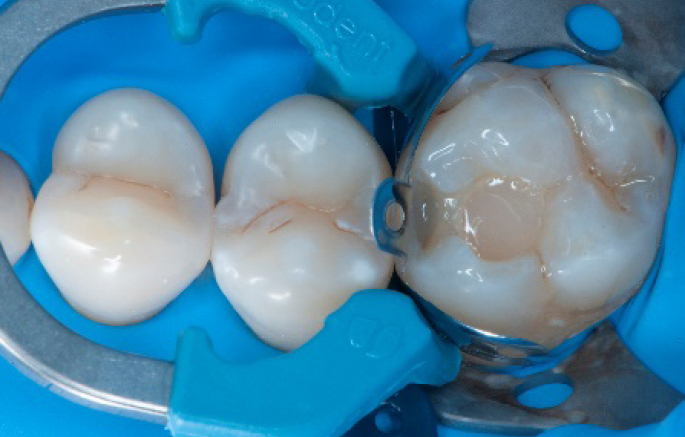

Step 1:

The situation after rubber dam isolation.

Step 2:

Initial cavity preparation, protecting the adjacent tooth with a Palodent1 WedgeGuard.

Step 3:

Class II cavity prepared.

Step 4:

The complete Palodent1 system in place: sectional matrix, wedge and ring.